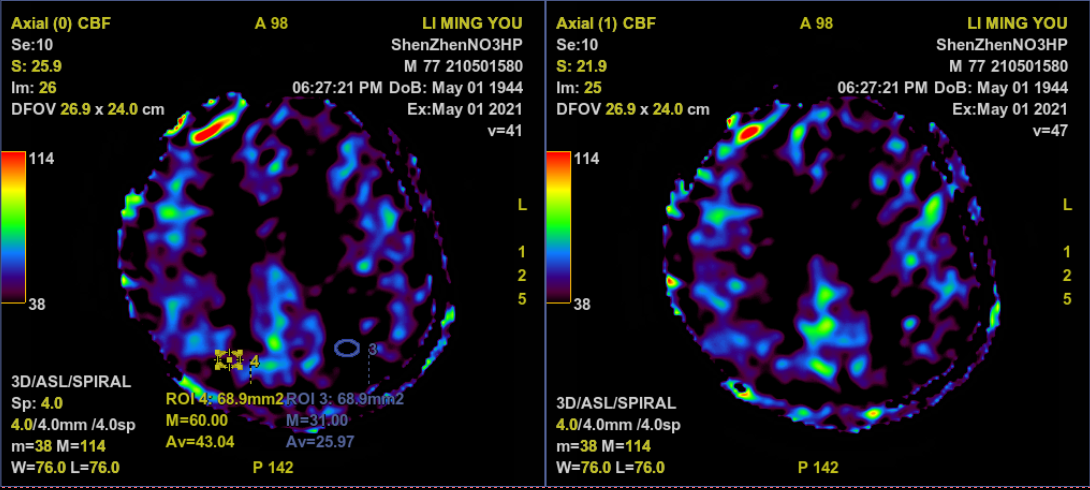

PWI示左侧大脑半球低灌注

术后无新发神经功能障碍,右上肢远端肌力升至4级。MRI未见出血、新发梗死;MRA示左侧颈内动脉管径基本恢复正常;PWI示左侧大脑半球灌注增加